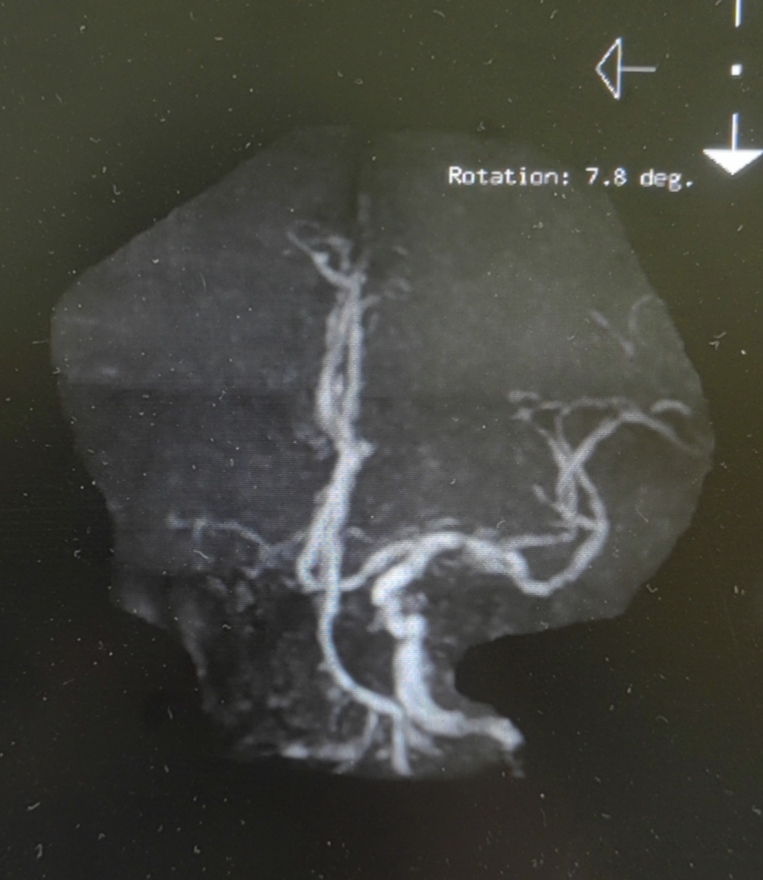

颈总巨大斑块急性闭塞的血管内治疗(双颈动脉支架桥接+支架释放后掉斑块,抽吸取栓)

急诊上台。